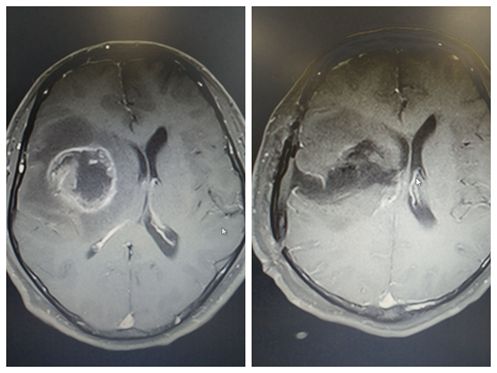

术前、术后患者脑部检查对比

2月23日,袁贤瑞教授带领其团队为翦先生精准切除了肿瘤。术中见病变位于右额叶内侧,肿瘤大小约5×4×5cm,灰红色,周围脑组织水肿,肿瘤深达内囊。7个小时,袁贤瑞教授利用先进技术的帮助及个人经验及手术技巧在显微镜下荧光显影全切肿瘤,顺利完成手术。